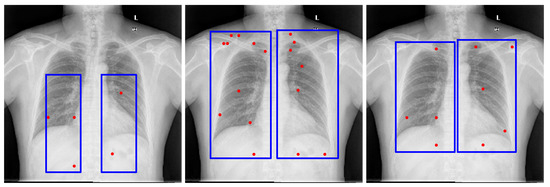

Figure 2. Examples of lung bounding box estimations generated by different models: LLaMA-4-Maverick-17B-128E, GPT-4o, and Gemini Pro 2.5. The blue rectangles indicate the bounding-box prompts, and the red dots represent the point prompts. Both are provided as inputs to the Segment Anything Model (SAM) to generate segmentation candidates.

4.5.4. Prompt Engineering and Choice of Large Vision-Language Models for Bounding Box Estimation

To derive reliable bounding box priors, we designed structured prompts that explicitly defined both the target anatomical structures and the spatial constraints of the bounding box. The final prompts used in our pipeline are provided in Appendix B. These prompts were tested across several LVLMs, including maverick-llama-4, GPT-4V, and Gemini Vision. While multiple models could generate bounding boxes, we selected Gemini Pro 2.5 for its consistent alignment with regions of interest and compatibility with available computational resources. In contrast, alternative models often produced loose or misaligned boxes, which degraded downstream segmentation accuracy. Representative bounding box results from different models with the same prompt are shown in Figure 2, underscoring the importance of prompt engineering and the sensitivity of the pipeline to LVLM choice.

GPT-4o [13] demonstrated performance comparable to Gemini Pro 2.5 [9] in our internal evaluations; however, Gemini Pro 2.5, available from Google, was chosen for downstream experiments due to its consistent accuracy, stable API access, and available research funding for sustained API usage. It also outperformed LLaMA-based models, as shown in Figure 2. Model outputs were returned in JSON format and integrated directly into our segmentation pipeline. While the bounding box estimations generated by Gemini across multiple datasets were not sufficiently precise to serve as final segmentations, they consistently localized the region of interest. Despite occasional boundary inaccuracies, these estimations provided reliable spatial priors that effectively guided the SAM model towards more accurate segmentations, as illustrated in Figure 3.